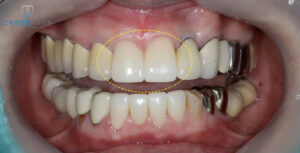

화서동치과 스마트한결의

치료 전후 사진이에요.

주변 치아와 자연스럽게 어우러지는

색상과 심미적인 형태로

회복된 모습이 보이시나요?

하지만 치료 후에는

앞니 색상과 형태가

자연스럽게 조화를 이루면서,

자신 있게 미소를 지으실 수 있게 되었다고

만족감을 표현해 주셨어요.^^